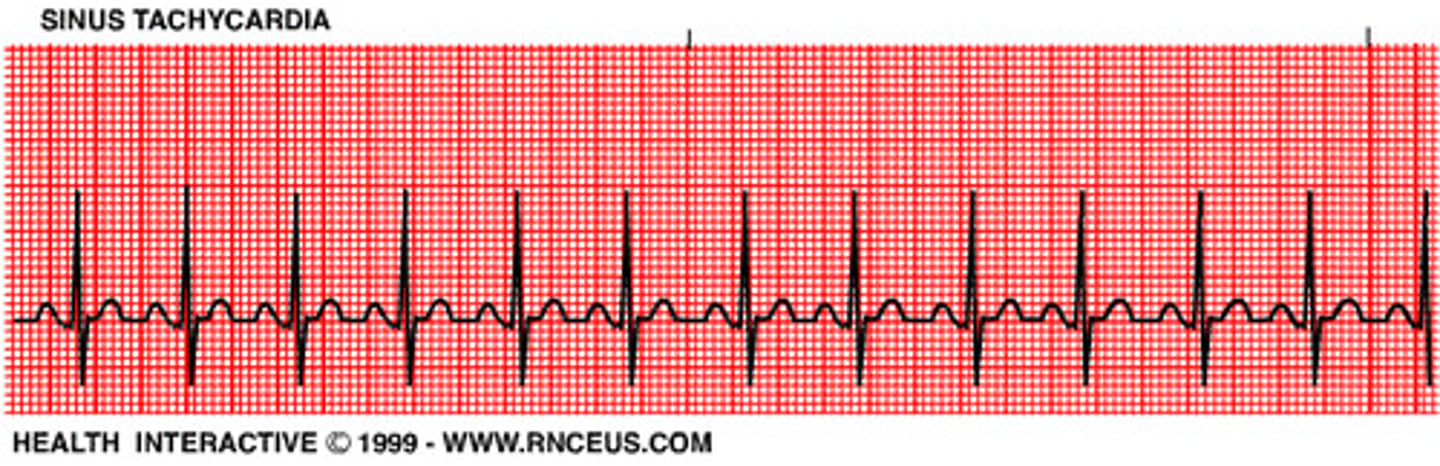

What is sinus tachycardia?

100-150bpm. rhythm is normal but too fast. workload of the heart is increased while the perfusion is decreased. this is a normal response to the body's increased demand for O2

What is the treatment for sinus tachycardia?

treat the cause: pain, hypovolemia, fever, exercise, anxiety, medications that stimulate sympathetic response, stimulants, illicit drugs